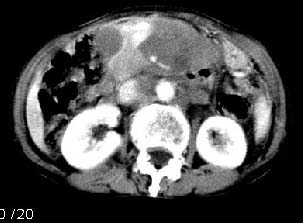

胰腺受压前移,胰管扩张,应为腹膜后占位,病灶密度不均,有低密度坏死区,强化扫描强化不明显腹腔干动脉受侵,考虑腹膜后恶性占位

我的第1诊断还是考虑是淋巴类病变1}。从病灶形态上看不是很规则,但其更向是多个结节的融和,其内有少许坏死,整个病灶的强化不是很明显,临近左恻肠间隔有增厚,2}我认为更重要的一点的是肠系膜有明显增厚呈片状。3}患者的脾脏不大其未见异常病灶。结合以上几点我首先考虑是转移性{但对此诊断我觉得不足之处;转移性的淋巴结肿大融合为什么没有坏死?}。{另外患者无大便习惯改变及血便,其发现右颈包块在今年过年无意发现}。以上是我的浅分析望各位战友继续讨论!谢谢!!

主动脉-胰腺间隙可见巨大分叶状软组织肿块影,包绕腹主动脉、腹腔干及其分支、腔静脉等大血管,增强呈无明显强化,临近脏器明显受压移位,增强示有分界。肝右叶可见局限性低密影,边缘清楚。

再看从肠系膜根部到胰腺后主动脉及上腔静脉周围可见相连的较大的软组织肿块影,形态不规则,呈明显

的大小不等的分叶状,其中密度较均匀但其中可见条状低密度区,肿块边缘比较清晰周围的小肠受压移位

明显且堆积。

增强所见,腹腔动脉,肠系膜上动静脉被肿块包绕,结合平扫的条状低密度区恰好位于血管周围,较大的

肿块强化不明显(遗憾的是没有标上ct值)但胃壁强化的十分明显。

讨论:首先看肠系膜和腹膜后的肿块我认为是多发融合的肿大的淋巴结。理由1大小不等的分叶,分布比较

自由。2其中的包绕的血管和周围少量的脂肪即所说的。

同时胃的影象表现和临床的不典型表现,所以我认为淋巴瘤,临床表现不支持胃癌